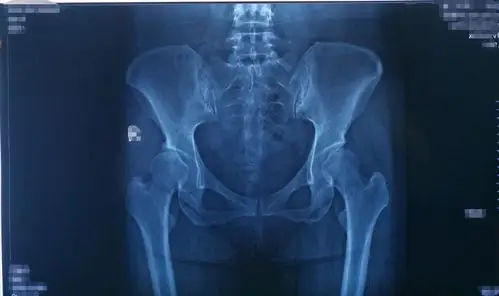

髋臼发育不良#医学影像 #医学科普 #放射科 #诊室日常 # - 抖音

髋臼发育不良半年,x线片显示,右侧髋臼顶平缓,股骨头-髋臼接触充分